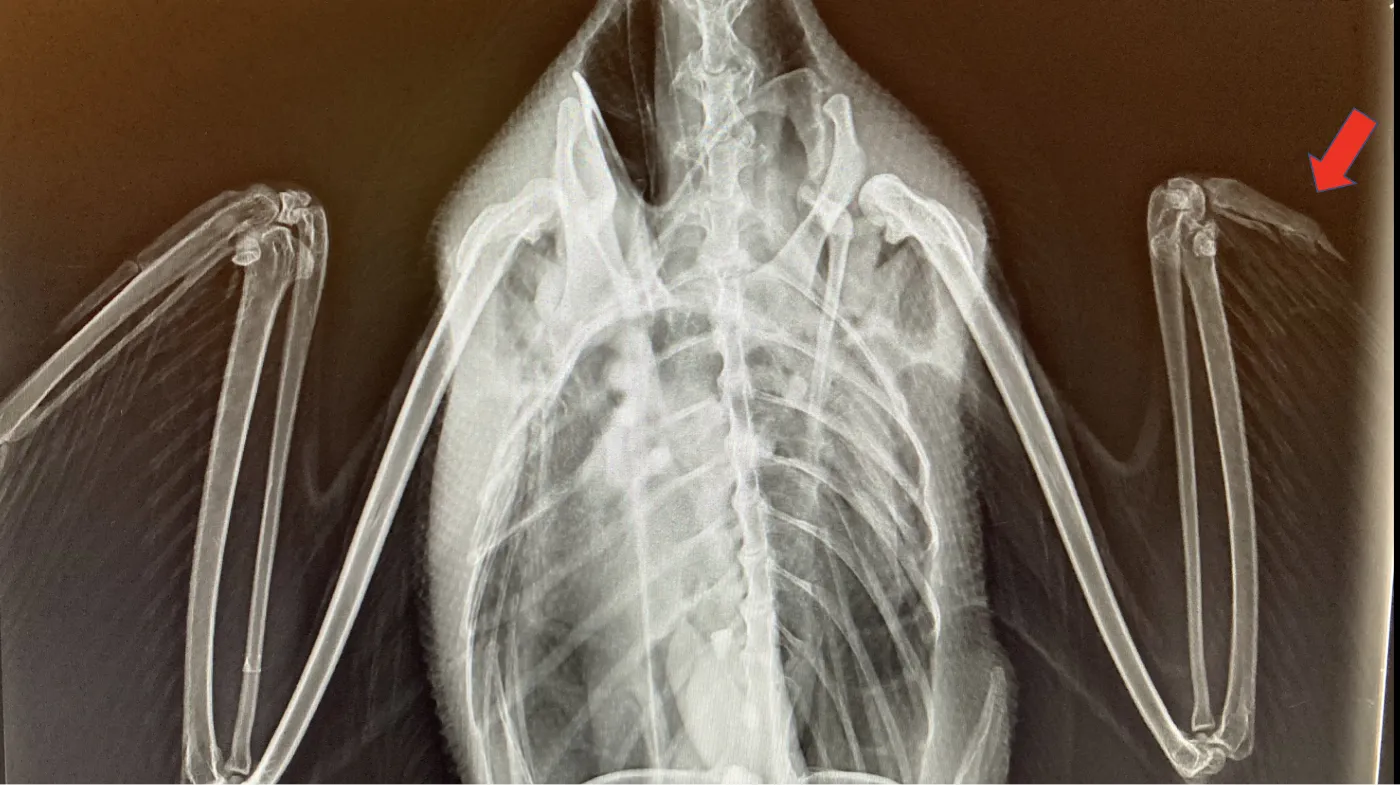

Physical Injuries

Territorial fights cause wounds, but boat propeller strikes from human activity are more visible and severe. Look for limping, unbalanced swimming, or exposed injuries.

X-ray image of a loon with a broken wing from a boat propeller injury

Wildlife rehab centers like Wild & Free document these cases. Leg injuries mimic normal postures—see leg positions below.